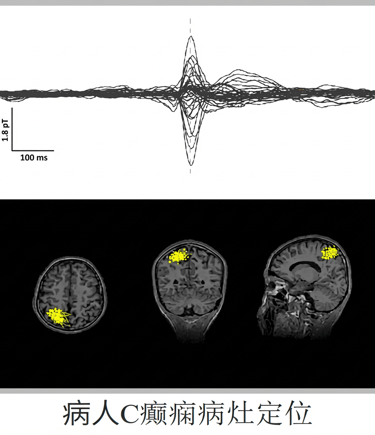

癲癇致癇灶定位

癫痫病例